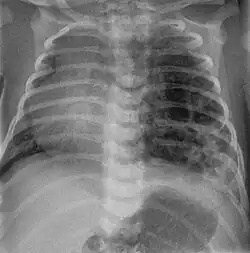

Zystisch adenomatoide Malformation bei einem Neugeborenen in der Röntgenaufnahme des Thorax. Man erkennt die großen zystischen Veränderungen der linken Lunge, die durch ihre raumfordernde Wirkung zu einem Mediastinalshift nach rechts geführt haben.